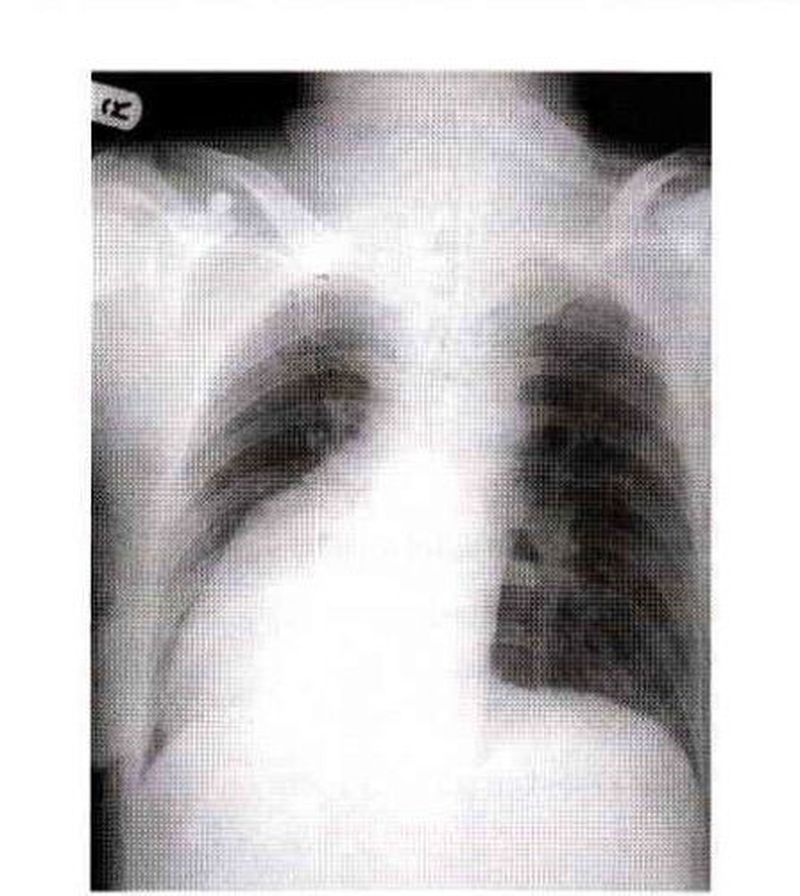

Normally the cardiac apex or apex beat is on the left side. In the condition called dextrocardia, the apex is on the right side. Dextrocardia may be part of a condition called situs inaersus in which all thoracic and abdominal viscera are a mirror image of normal.